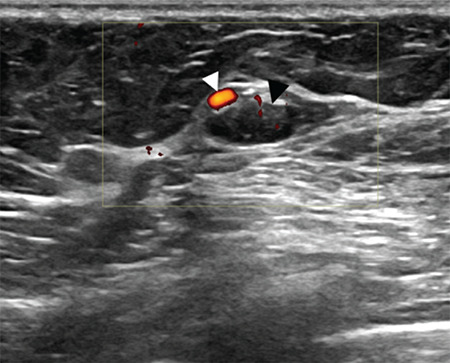

We present the case of a forty-year-old asymptomatic female with no personal or family history of breast cancer, who underwent a core needle biopsy (CNB) following the identification of a focal asymmetry in the right breast on screening mammography. Eight months later, a prominent adjacent vascular structure with a round outpouching was detected on breast ultrasound, confirmed as a post-biopsy pseudoaneurysm. Breast pseudoaneurysms, although exceedingly rare, result from inadvertent vessel puncture during core needle biopsies, particularly when larger gauge needles are used. They present as palpable, throbbing lumps in the breast and are well-defined heterogeneous structures that exhibit turbulent flow with a feeding artery on color Doppler imaging. This swirling sign showing a to-and-fro waveform is also known as the "yin-yang" sign on Doppler ultrasound. Post-CNB pseudoaneurysms in the breast, while rare, should be considered as potential complications following core need biopsy. Understanding their characteristic imaging features, risk factors, and available management options is essential for early diagnosis and appropriate treatment. This case underscores the importance of vigilance in biopsy procedures and the need for prompt recognition and intervention in case of such complications.

本病例是一名四十岁的无症状女性,无个人或家族乳腺癌病史,在乳房 X 光筛查中发现右侧乳房有局灶性不对称,随后接受了核心针活检(CNB)。八个月后,她在乳腺超声波检查中发现了一个突出的邻近血管结构,并伴有圆形外囊,证实为活检后假性动脉瘤。乳腺假性动脉瘤虽然极为罕见,但却是在核心针活检过程中不慎刺穿血管造成的,尤其是在使用较大规格的针头时。乳房假性动脉瘤表现为乳房内可触及的搏动性肿块,是界限清晰的异质结构,在彩色多普勒成像中表现为进血动脉的湍流。在多普勒超声检查中,这种显示往返波形的漩涡征也被称为 "阴阳 "征。乳腺核芯穿刺活检后假性动脉瘤虽然罕见,但应被视为核芯穿刺活检后的潜在并发症。了解假性动脉瘤的影像学特征、风险因素和可用的治疗方案对于早期诊断和适当治疗至关重要。本病例强调了在活检过程中保持警惕的重要性,以及在出现此类并发症时及时识别和干预的必要性。